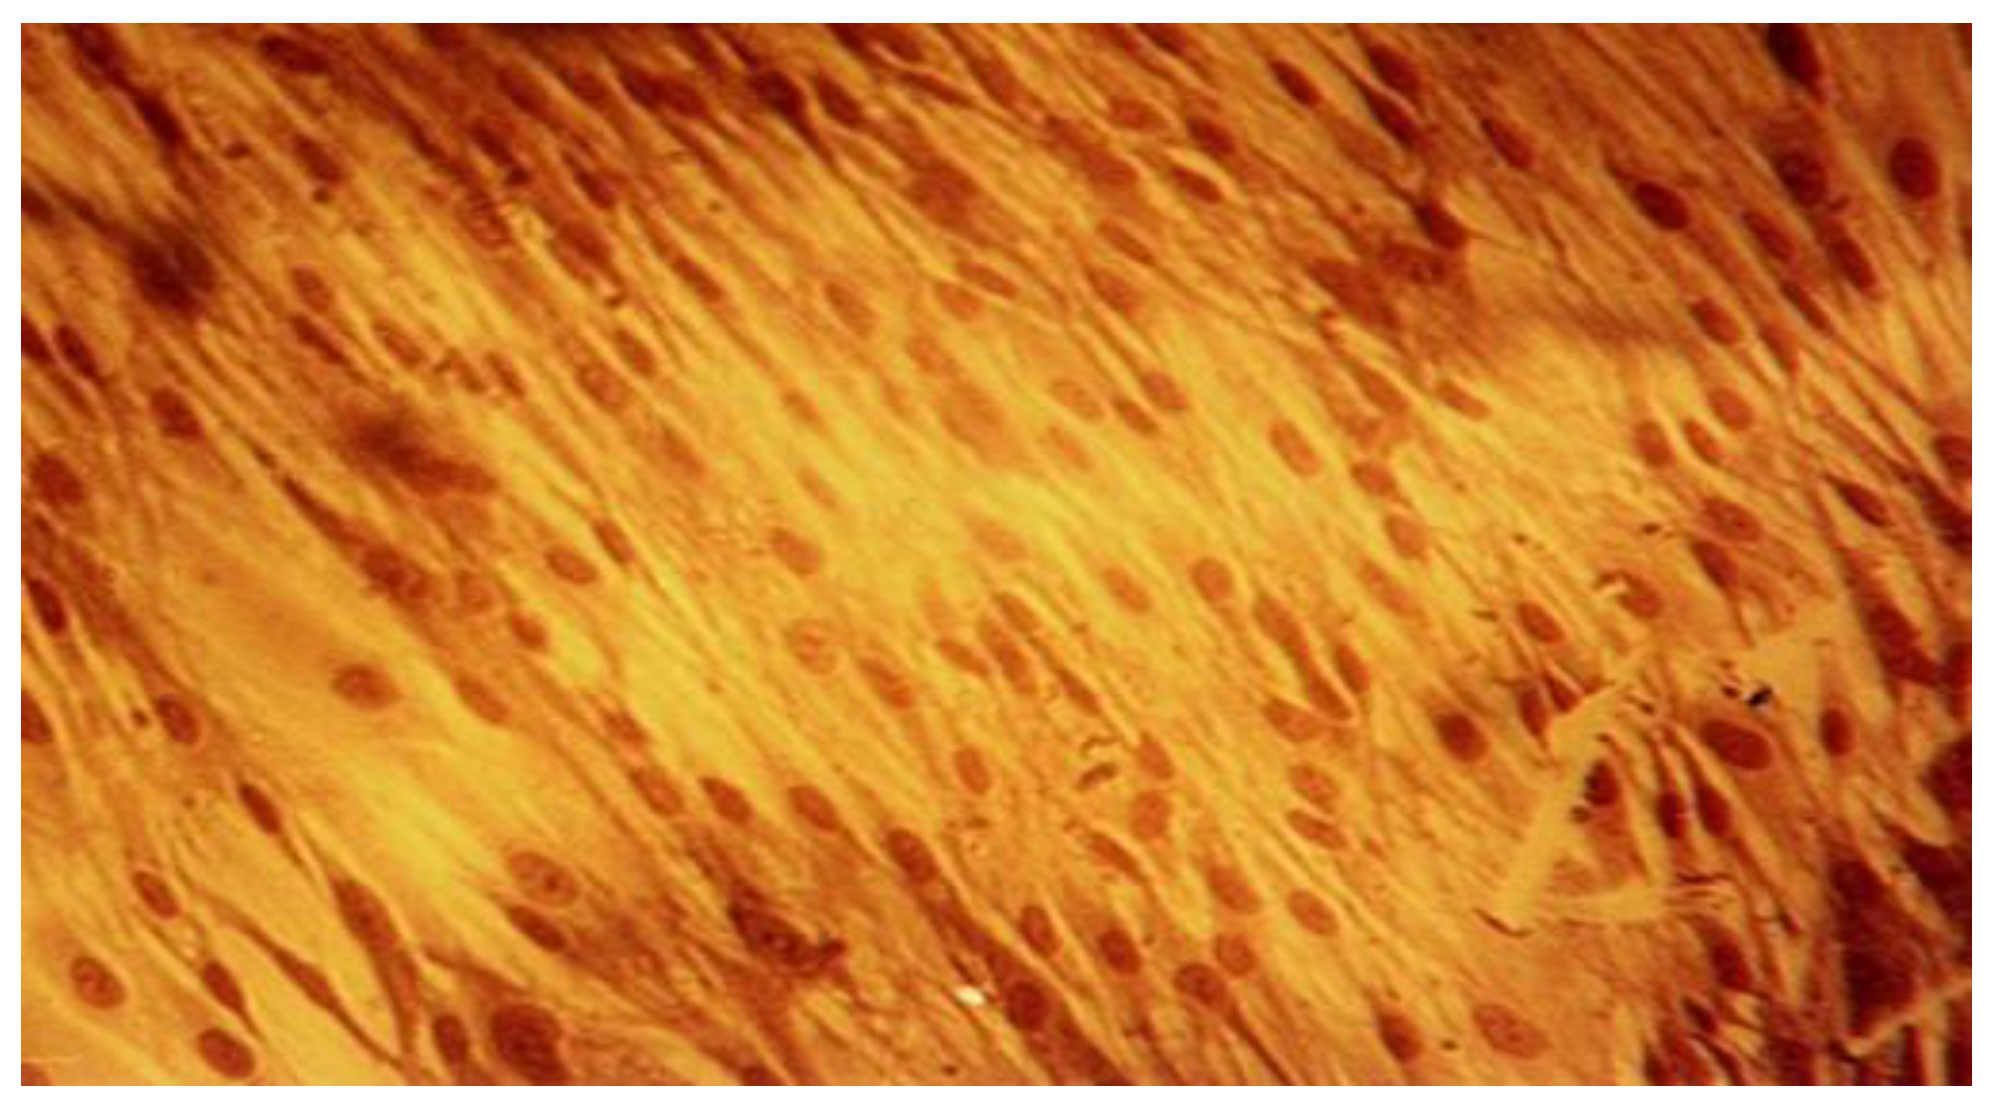

Figure 7.

Fibroblasts cell line L929 at 24-hour mark, Biodentine lot, 20x magnification. Cell membrane damage in association with nuclei alterations.

Figure 8.

Fibroblasts cell line L929 at 96-hour mark, Biodentine lot, 40x magnification. Numerous cellular morphological alterations and floating dead cells.

The qualitative assessment of biological effect by microscopic examination of cellular appearance is consistent with values for the cellular dead rates and cellular density. Different changes in general cellular morphology, whose progressive evolution during the experiment, conducted to death cell, and detachment from substrate, have been observed. The observations indicate more obvious and visible aspects for MTA HP than BD and they have been presented descriptively. Nevertheless, the microscopic evaluations are in general more difficult to be precisely identified and must be always referred to the entire experiment and numerical data obtained. For MTA HP, more visible cell membrane integrity damages were observed, in association with a higher number of floating death cells. Loss of membrane integrity is a clear indicator for an unfavorable prognosis for cell survival [26]. For BD the morphological degenerative cell alterations were more discrete, and the presence of round detached cells less important. The rounded aspect is related to first sign of cellular injury, swelling, later followed by different nuclei and nucleoli alterations. No clear-cut delimitation between the healthy and affected cells were observed.